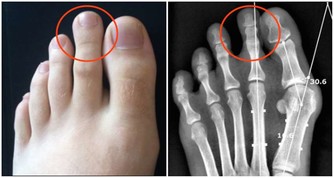

注意:免疫力並非越強越好,太高也是病,會引起類似紅斑狼瘡、類風濕等自身免疫性疾病。